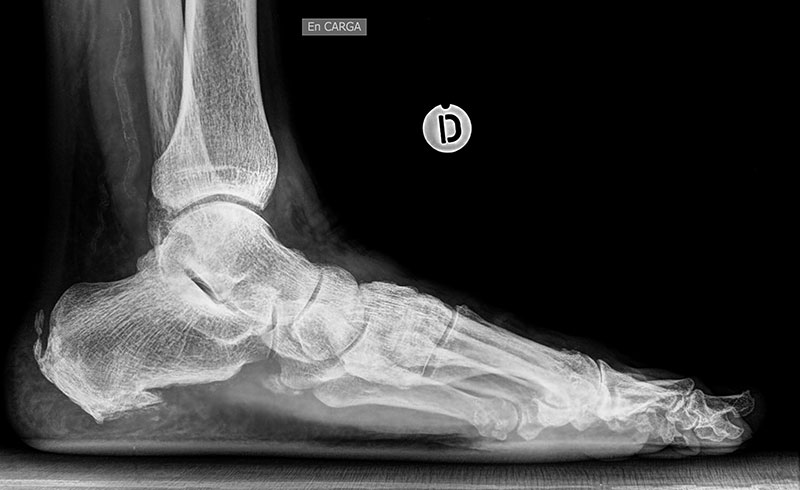

En las deformidades flexibles de retro y mediopie (pie plano, pie cavo) así como en algunos casos de artrosis de tobillo (artrosis asimétrica) abogamos por la preservación articular realizando osteotomías correctoras sin afectar a la movilidad articular.

El tipo de osteotomías, así como los gestos quirúrgicos complementarios será personalizado según la deformidad que presente el paciente.

Antes